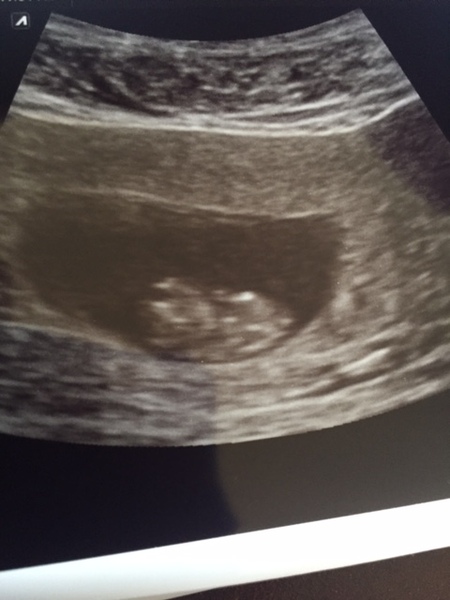

9 week foetuses look a bit like aliens; or at least mine does! Can't wait until the next scan when s/he will look a little more human Smile

May glad the scan went well. He looks like he's just starting to turn people shape Smile

Lovely scan picture May.

Lovely scan May.